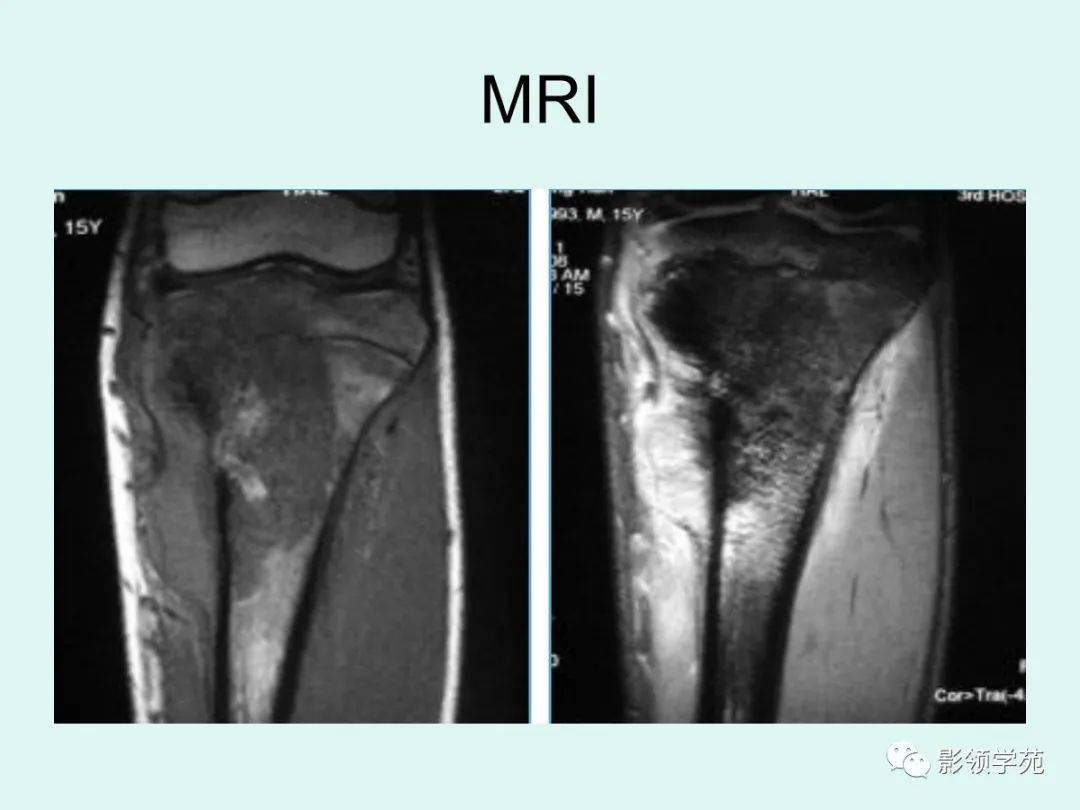

骨肉瘤影像学

骨肉瘤影像学,骨肉瘤恶性肿瘤

10种类型骨肉瘤影像学诊断